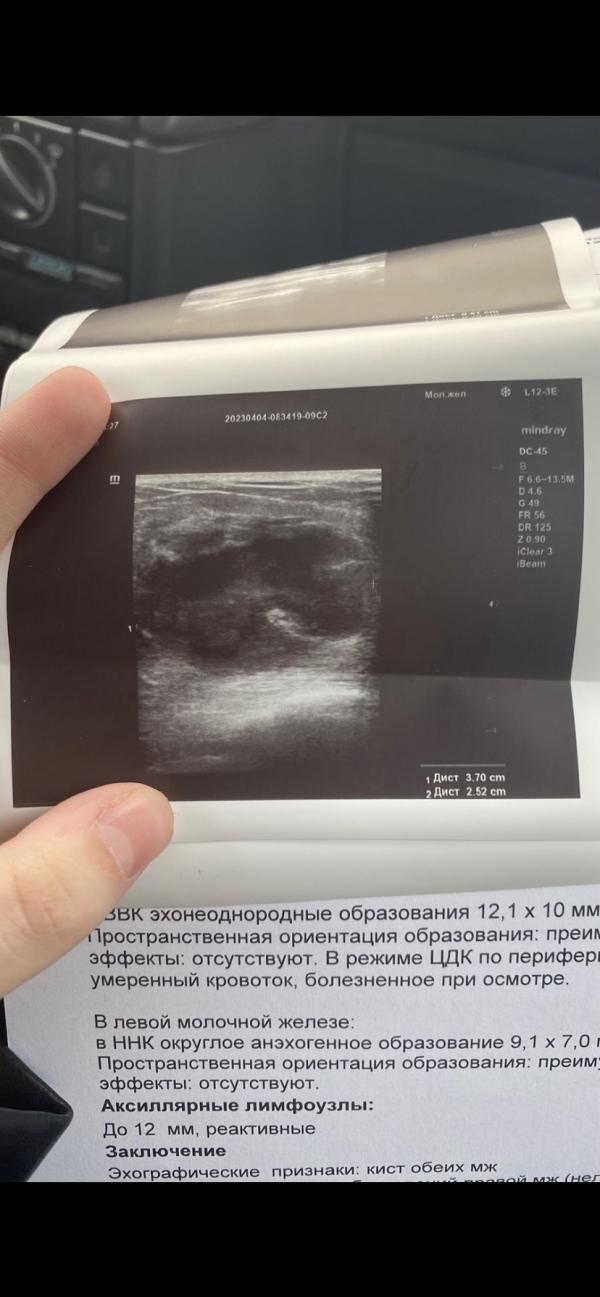

Часто стали попадаться посты про лактастаз / мастит, пожалуй расскажу свою печальную историю подробней. Фото не для впечатлительных. Ну и напомню себе как делать НЕ надо. Воскресенье 26 марта, 23 дня как родила, малышка малососущая, но постоянно висячая на груди. Просыпаюсь и чувствую уплотнение НАД правой грудью, небольшое, болезненное, не заметное для окружающих, но напрягло. Говорю сразу, температуры, покраснения и еще чего подобного не было. Ладно, сцеживаюсь, массажи, контрастный душ, все...